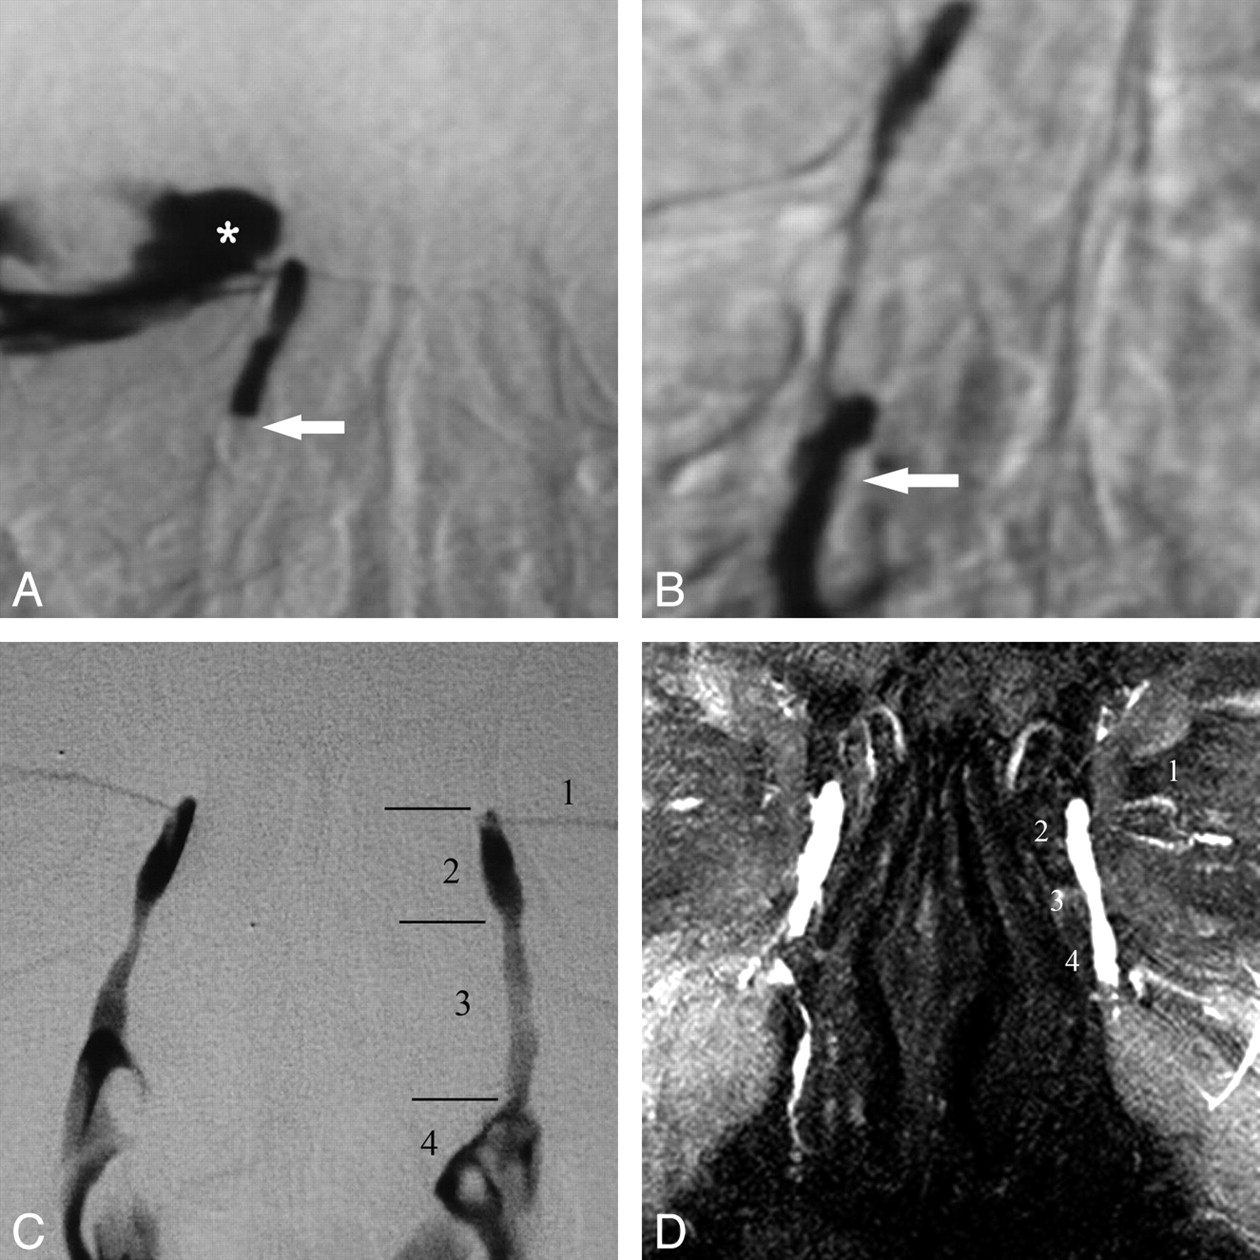

DS and MR DCG 12-year follow-up after balloon DCG in an asymptomatic patient. A, DS DCG reveals occlusion of the distal NLD (arrow) and reflux of iodinated contrast material to the conjunctival sac (asterisk). B, DS DCG immediately after transluminal balloon dilation shows passage of the contrast media to the inferior meatus of the nasal cavity (arrow). Note that there is no reflux to the conjunctival sac after successful balloon DCG. C, Twelve-year DS-DCG follow-up with bilateral simultaneous contrast media injection reveals a completely normal LDS. The anatomic regions of the normal left LDS are the following: 1) inferior canaliculus, 2) lacrimal sac, 3) NLD, and 4) contrast media in the nasal cavity. D, Bilateral topical contrast-enhanced coronal MIP DCG image from 3D FSPGR sequence demonstrates patency of the LDSs both on the intervened right side and normal left side. 1 indicates the canaliculi; 2, lacrimal sac; 3, nasolacrimal duct; 4, contrast media in the nasal cavity.